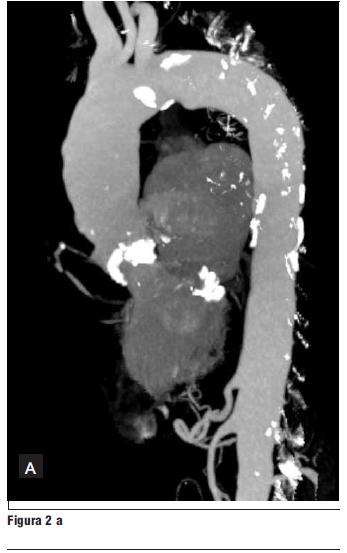

Log EuroSCORE (European System for Cardiac Operative Risk Evaluation): 11,07%.

Visto el caso en ateneo médico quirúrgico y en conjunto con el paciente, dado que fue intervenido con cirugía de revascularización miocárdica en dos oportunidades, se decide evaluar la factibilidad del implante percutáneo de válvula aórtica para lo cual se realizó angiotomografía de aorta y miembros inferiores con tomógrafo multicorte de 16 filas de detectores. Se realizaron reconstrucciones 3D de aorta toracoabdominal y estudio con contraste. Dicho estudio mostró aorta con múltiples calcificaciones parietales sobre todo en aorta ascendente próxima a la válvula y valvulares, en cayado y aorta abdominal, sin disección. Diámetro de aorta en su origen 31 mm, aorta ascendente 26 mm. Sin estenosis en arterias del cuello; aorta abdominal de calibre habitual; arterias ilíacas y femorales de calibre habitual y sin imágenes de estenosis. Diámetro del anillo: 24 mm, altura del sinus: 15.5 mm, diámetro de raíz de aorta: 30,0 mm, arteria femoral izquierda: 8,6 mm, arteria femoral derecha: 8,4 mm (figura 1).

Se realizó coronariografía con estudio hemodinámico y medidas aórticas que mostraron: oclusión en la unión de tercio proximal y medio de descendente anterior, lesión severa en el origen de fino ramo diagonal, restenosis moderada intrastent de circunfleja y origen de primer marginal obtuso de fino calibre, ATC con stent de coronaria derecha con resultado mantenido, oclusión de puentes venosos de aorta a marginales y coronaria derecha, puente venoso aorto-diagonal permeable y sin lesiones, anastomosis mamaria interna izquierda-descendente anterior permeable con buen flujo y sin lesiones. Medidas hemodinámicas: presión arterial 110/80 mm Hg, media 100 mm Hg, leve incremento de presión diastólica final de VI 200/20 mmHg, gradiente transvalvular aórtico pico 90, medio 55 mm Hg. Medidas aórticas: altura del seno de Valsalva: 17,5 mm, diámetro de raíz de aorta: 28 mm, arteria femoral izquierda 8,7 mm, arteria femoral derecha: 8,1 mm.

Figura 1. Angiotomografía (AngioTC) de aorta y miembros inferiores. Las imágenes blancas en placas corresponden a calcificaciones.